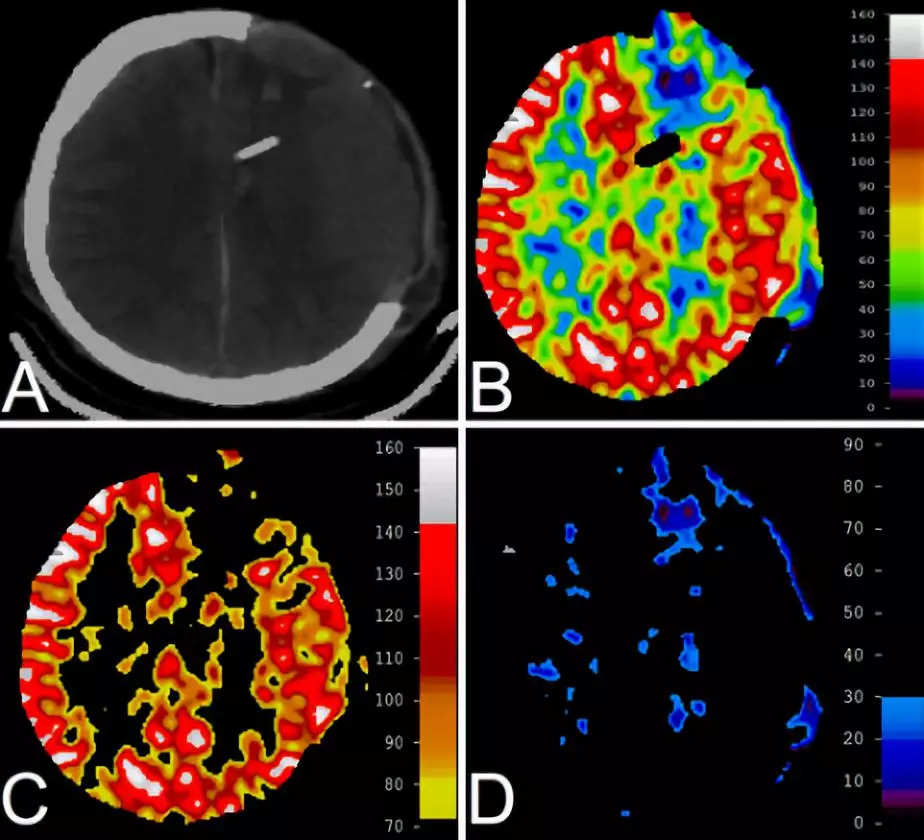

30.颅脑损伤去骨瓣减压后氙气增强CT定量观测脑血流量

Quantitative cerebral blood flow using xenon-enhanced CT after decompressive craniectomy in traumatic brain injury.

PMID: 29027859 DOI: 10.3171/2017.4.JNS163036

去骨瓣减压术是治疗创伤性脑损伤(traumatic brain injury, TBI)的有效方法,但并不是所有创伤性脑损伤患者都能获益。患者的不良预后与脑水肿、脑血流量(cerebral blood flow, CBF)改变和代谢功能障碍有关。本研究利用氙增强CT定量测定CBF,探讨创伤性脑损伤患者去骨瓣减压术后的全脑和骨瓣缺损下局部CBF模型。

结果显示,去骨瓣减压术后大多数患者的全脑CBF正常和充血;去骨瓣减压术后持续性脑灌注不足与重度TBI后的早期死亡率相关。

【吴宁波】